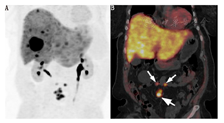

结合PET/CT的自身优势(更高的空间分辨率和灵敏度)并通过改良药理特性,将能检测较小病变或中度SSTR表达的病变,提高诊断的灵敏度和准确性(图1和图2)。

68Ga-肽PET显像在非胰腺和胰腺NETs有类似的作用(图1,图2,图3)。68Ga-肽PET显像对1型多发性内分泌腺瘤也很灵敏。在19例1型多发性内分泌腺瘤患者中进行68Ga-DOTATOC与111In-喷曲肽及增强CT的对比研究,结果显示68Ga-DOTATATE检出NETs的灵敏度为76%,111In-喷曲肽为20%,增强CT为60%;68Ga-DOTATOC检出胰腺肿瘤46个,111In-喷曲肽检出11个,增强CT检出37个[29]。一项前瞻性研究包括26例1型多发性内分泌腺瘤,对患者行68Ga-DOTATATE、111In-喷曲肽和增强CT,结果显示68Ga-DOTATATE PET/CT显像检出107个病灶,111In-喷曲肽SPECT/CT检出33个病灶,增强CT检出48个病灶;26例患者中8例(31%)因68Ga-DOTATATE PET/CT的结果而改变治疗计划,而111In-喷曲肽SPECT/CT或CT无阳性发现[30]。